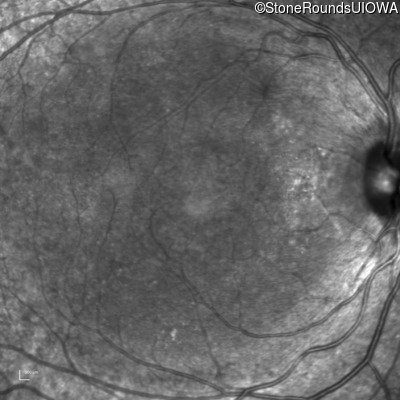

Blue Autofluorescence - Right - 20/25 -1

Exemplar